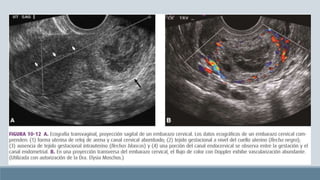

Embarazo cervical

Frecuencia

incrementada por ART

Por cada 100 o 200

nacidos vivos

Es mayor en multíparas

El 60% de EC tuvieron

antes una dilatación y

legrado.

Métodos

El 90% de mujeres con EC

manifiesta hemorragia

vaginal indolora

25% refiere dolor

abdominal

33% hemorragia extensa

Paredes cervicales

distendidas y delgadas y el

orificio externo se dilata

Caso mas avanzado: 14

semanas

Exploración con espejo

vaginal, palpación y

ecografía transvaginal

Resonancia magnética y

ecografía tridimensional

Entre mas alto se implante el trofoblasto en el canal cervical mayor su

potencial para crecer y sangrar

Embarazo cervical Frecuencia incrementada porART Por cada 100 o 200 nacidos vivos Es mayor en multíparas El 60% de EC tuvieron antes una dilatación y legrado. Métodos El 90% de mujeres con EC manifiesta hemorragia vaginal indolora 25% refiere dolor abdominal 33% hemorragia extensa Paredes cervicales distendidas y delgadas y el orificio externo se dilata Caso mas avanzado: 14 semanas Exploración con espejo vaginal, palpación y ecografía transvaginal Resonancia magnética y ecografía tridimensional Entre mas alto se implante el trofoblasto en el canal cervical mayor su potencial para crecer y sangrar Tratamiento Cerclaje Legrado y taponamiento Embolización arterial Metotrexato